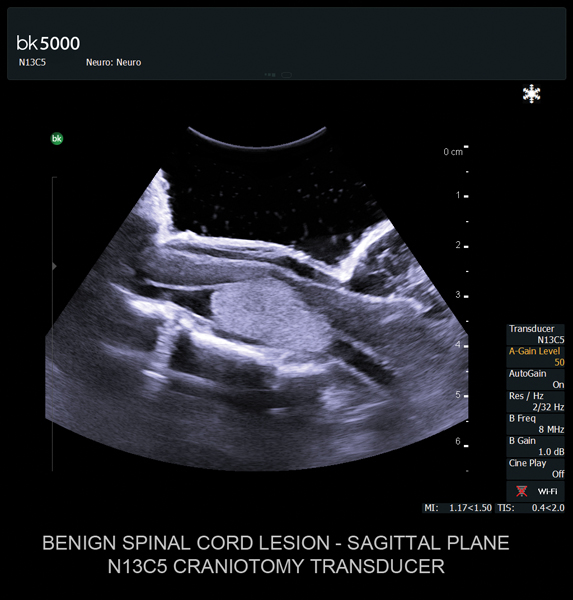

Ultrasound can improve neurosurgical procedures by helping you navigate and identify lesions and anatomical structures in real-time. This is particularly important as the data obtained from a preoperative CT or MRI scan can be outdated at the time of surgery. The bk5000 neurosurgical system provides the highest quality images that allow you to clearly see the margins of a lesion and to determine the best course of action. Using advanced graphics processing technology, this powerful system provides immediate, auto-optimized images that allow you to see the information you need, faster.

Transducers designed for Neurosurgery

The specialized, high-resolution, sterilizable neurosurgery transducers enable you to obtain detailed images of the brain and spinal cord. They have a convenient Smart™ button that lets you activate the transducer, then freeze, store or print the images at the press of a button. Disposable, easy-to-use needle guides assist with targeting lesions.